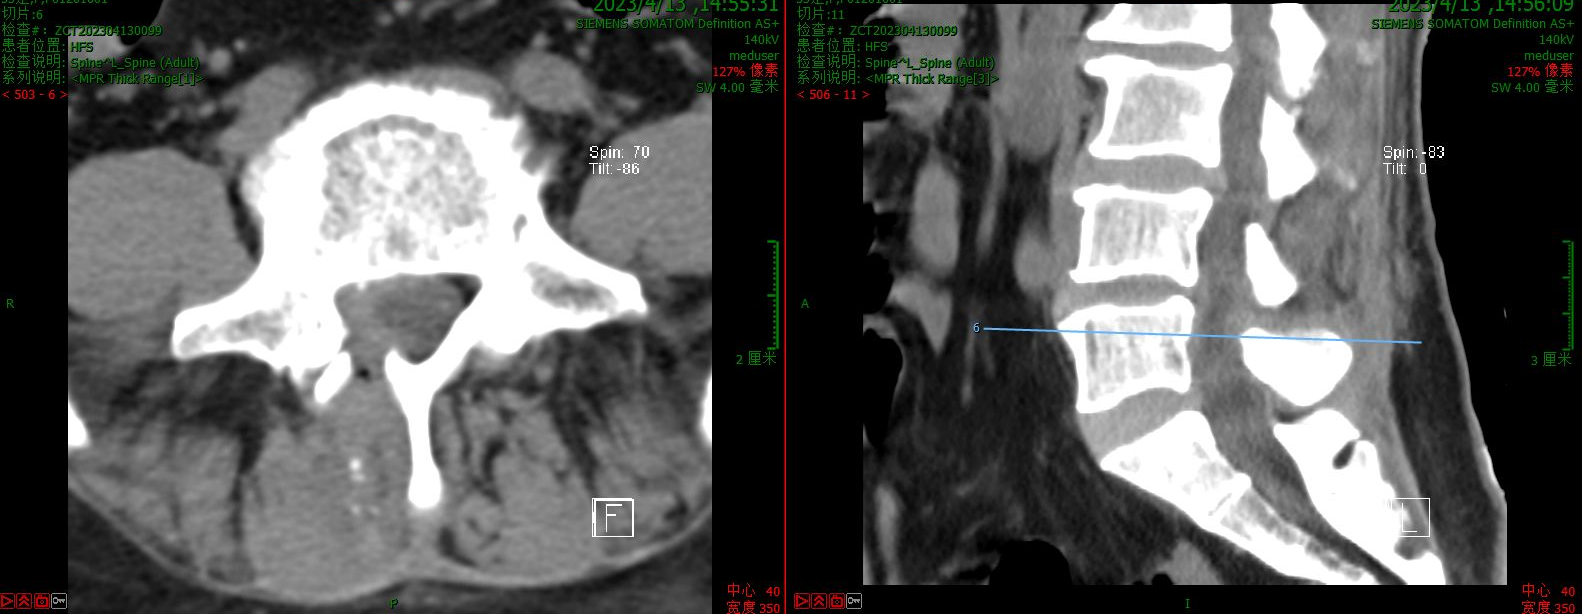

第二例病例为腰椎峡部裂患者。为其实施了VBE下的经椎间孔椎间融合术(TLIF)。患者术前腰痛伴右大腿后方疼痛1年余。术后第二天可下床活动,腰腿痛缓解。

术前CT